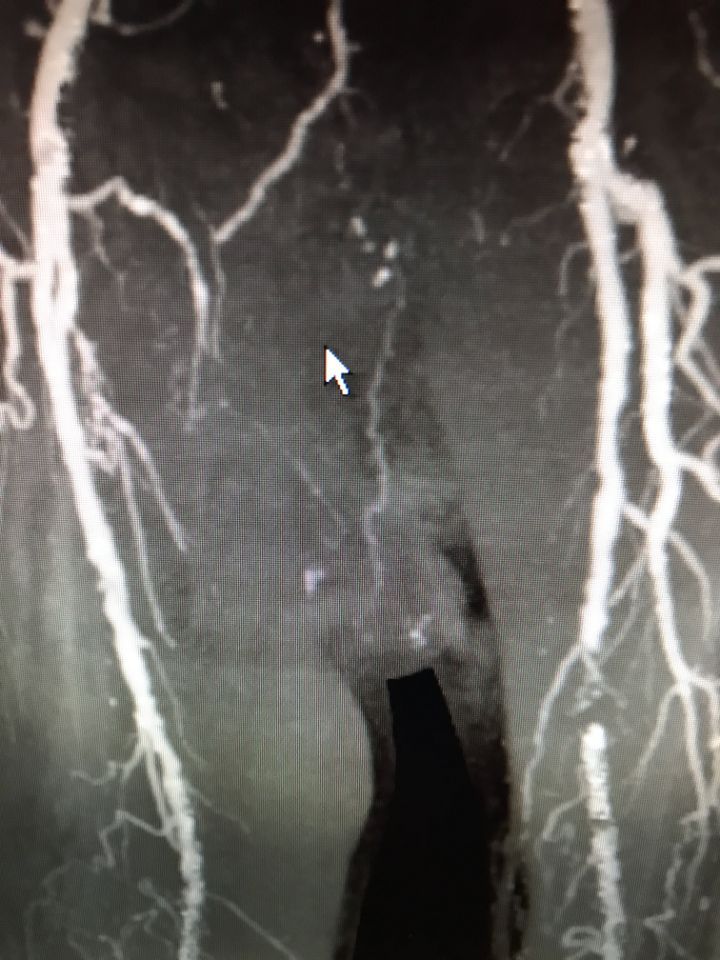

Ecco alcune immagini degli interventi eseguiti dal Dottor Viglione presso il suo studio a Cuneo.